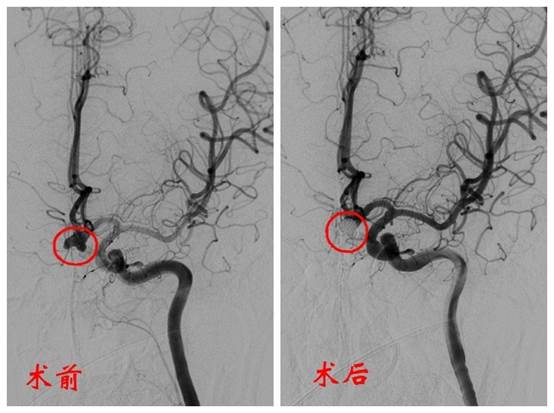

神经外科介入团队紧急开展DSA血管造影术和经导管颅内动脉瘤介入栓塞术。

介入栓塞治疗就是通过细小导管将弹簧圈填塞进动脉瘤瘤体,防止血液流入瘤体,避免动脉瘤再次破裂出血。

术中发现,动脉瘤直径约8-9毫米,有三个凸起,类似枫叶。动脉瘤不规则的形状增加了填塞的难度,手术团队历时两个多小时,填塞了十多个弹簧圈才顺利完成手术。

术后CT显示患者颅内未见再发出血,原出血部位吸收良好。

手术前后对比图